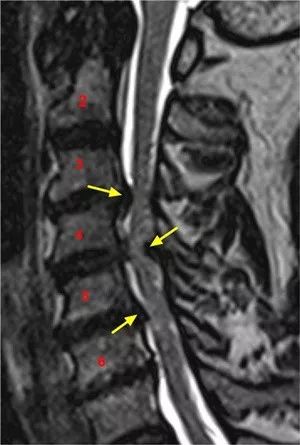

Cervical excitatoryneurons sustain breathing after spinal cord injury

颈兴奋神经元有助在脊髓损伤后维持呼吸

▲ 导读:呼吸功能障碍是颈椎创伤性脊髓损伤后发病和死亡的主要原因,常常需要辅助通气,因此需要制定恢复呼吸的策略。

作者在不同脊柱损伤模型中结合使用药物基因学和呼吸生理学分析,研究表明,颈椎中部兴奋性中间神经元的维护对维持非创伤性颈脊髓损伤小鼠的呼吸非常重要,同时对创伤性脊髓损伤后促进呼吸复苏也非常重要。

虽然这些中间神经元对于正常情况下的呼吸并非必要,但对未受伤动物体内的中间神经元进行刺激可以提高吸气幅度。

脊髓损伤后,通过药物立即刺激颈兴奋中间神经元可恢复呼吸运动功能。

总的来说,研究结果展示了一种通过靶向神经元亚群恢复中枢神经系统损伤后呼吸的策略。

图1:退行性颈椎病ntSCI患者的颈椎核磁共振成像。